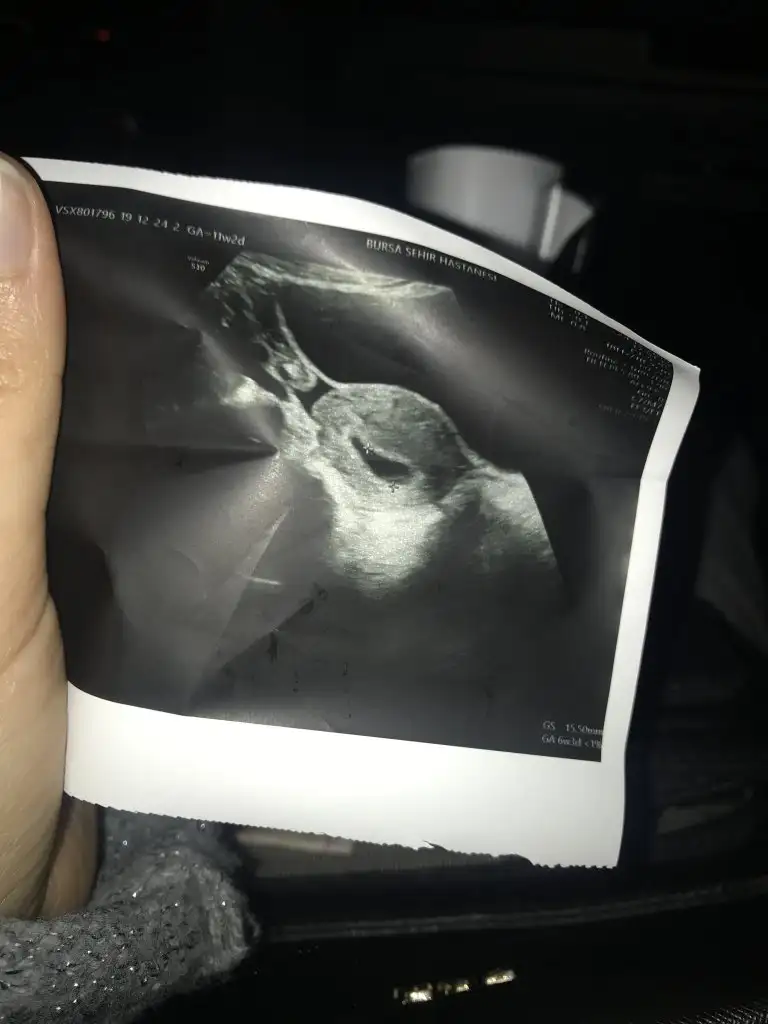

Yaaa cok sevındımmm:)kızlar drdan geliyorum keseyi gördük çok şükür haftaya kalp atışları için gidicez inşallah sıkıntısız duyarız

İnşallah haftaya hepimiz güzel haberler veririzkızlar drdan geliyorum keseyi gördük çok şükür haftaya kalp atışları için gidicez inşallah sıkıntısız duyarız

gözünüzaydın inşallh banada nasip olur keseyi görmek,kalp atışlarıda sıkıntısız duyarız inşallhkızlar drdan geliyorum keseyi gördük çok şükür haftaya kalp atışları için gidicez inşallah sıkıntısız duyarız

Ay gözünüzaydın maşallhEki Görüntüle 2568687 Tbizimkisi altı haftalık olmuş 10 sonra allah nasipederse kalp atışını duymaya gidicez![]()